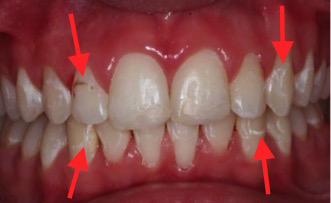

Cirka vart fjärde barn i Sverige behandlas med fast tandställning och upp till 50 % av dessa barn utvecklar så kallade ”White Spot Lesions” (WSL). Skadorna benämns WSL på grund av sitt oftast vitaktiga utseende, orsakat av ”urkalkning” av emaljen, och kan variera vad gäller antal drabbade ytor och utbredning på tanden (bild 1-2). Skadorna uppstår främst runt tandställningens fästen och kan upplevas som missprydande i och med att de ofta återfinns på framtänderna. Skadorna, som har en begränsad förmåga att spontant läka ut, kan liknas vid ett ärr som försämrar det slutgiltiga behandlingsresultatet.